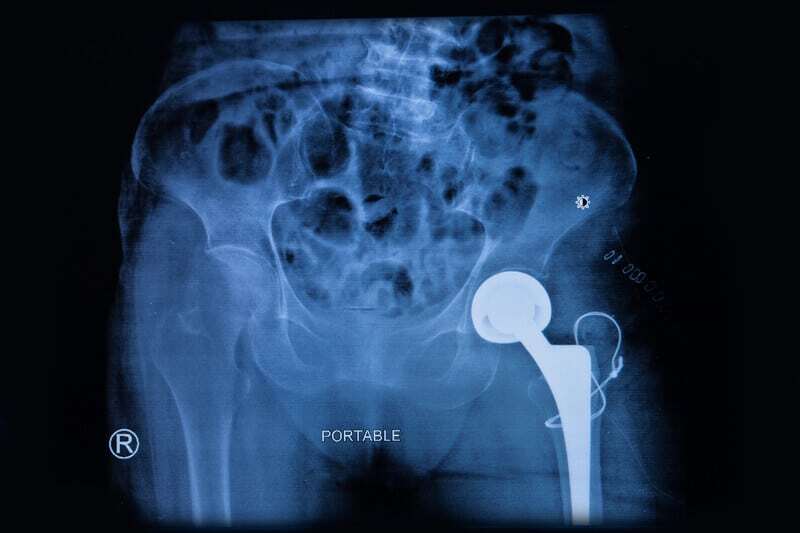

“From an orthopaedic perspective, elective operations for those suffering with what are often severe, life-limiting conditions were cancelled to allow health services to cope with the successive waves of COVID-19 patients. This has resulted in a staggering increase in waiting lists to levels that will take years to bring back under control. It has also resulted in twice the number of patients who are waiting for total hip or knee arthroplasty experiencing a state of life which can be considered as “worse than death”.”

Other unforeseen consequences may well be found as a result of the drug treatments used to combat the effects of the disease. “Glucocorticoids have been used to manage acute respiratory disease syndrome (ARDS) in COVID-19 patients, and have shown to be beneficial in reducing 28-day mortality and the need for mechanical ventilation. . . Ostensibly effective in the treatment of ARDS, the widespread use of such treatment may be a double-edged sword. The detrimental effects of steroids are well documented, and the link between these drugs and the occurrence of femoral head avascular necrosis (bone death common in advanced hip and talus osteoarthritis) is increasingly recognized. . . If the rates of avascular necrosis reach the heights of those reported following (COVID-19), then orthopedic services may be subject to a pandemic of avascular necrosis, and result in a significant increase in the burden of musculoskeletal disease in the community.”

“‘Long COVID-19’ can affect different body systems. At present, avascular necrosis as a consequence of ‘long COVID-19’ has yet not been documented. By large-scale use of life-saving corticosteroids in COVID-19 cases, we anticipate that there will be a resurgence of avascular necrosis cases. We report a series of three cases in which patients developed avascular necrosis of the femoral head after being treated for COVID-19 infection. The mean dose of prednisolone used in these cases was 758 mg (400-1250 mg), which is less than the mean cumulative dose of around 2000 mg steroid, documented in the literature as causative for avascular necrosis. Patients were symptomatic and developed early avascular necrosis presentation at an average of 58 days after COVID-19 diagnosis as compared with the literature which shows that it generally takes 6 months to 1 year to develop avascular necrosis post steroid exposure.”